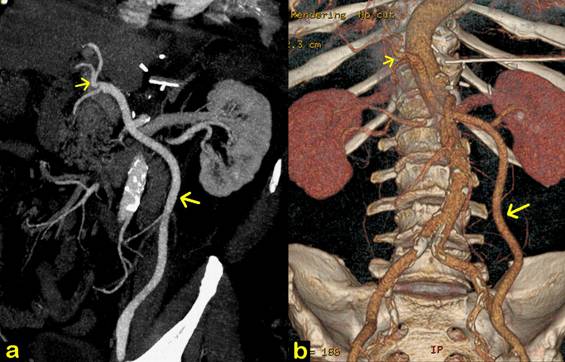

Patient did not receive transfusion and recovery was uneventful. Patient was discharged on the 10th postoperative day. Abdominal drain was removed on the 12th postoperative. Postoperative angio-CT disclosed a patent arterial bypass (Fig. 3). Patient is well and asymptomatic 13 months after operation. At the time of this writing, postoperative CT scan showed no evidence of disease and CA 19-9 level is normal.

FIGURE 3. Postoperative angio-CT scan.

a. Coronal view shows a patent Dacron vascular graft (large arrow). Hepatic artery is identified (small arrow).

b. Colour 3D reconstruction shows a patent left external iliac-hepatic arterial bypass (large arrow). Hepatic artery is identified (small arrow). Note diffuse calcification of abdominal Aorta and absence of celiac trunk. Abdominal drain can be seen.

In this particular case, collateral flow by pancreaticoduodenal branches did not guarantee adequate arterial blood supply to the liver. Moreover, due to extensive calcification, distal aorta, common iliac and right external iliac arteries were not suitable for anastomosis (Fig. 1d). Therefore, we elected the left external iliac artery for proximal vascular anastomosis. Regarding the vascular substitute, safena magna could be an option but it would be prone to excessive kinking or compression on its long retroperitoneal course. A Dacron vascular prosthesis was used instead, and postoperative angio-CT scan shows adequate graft patency (Fig. 3).